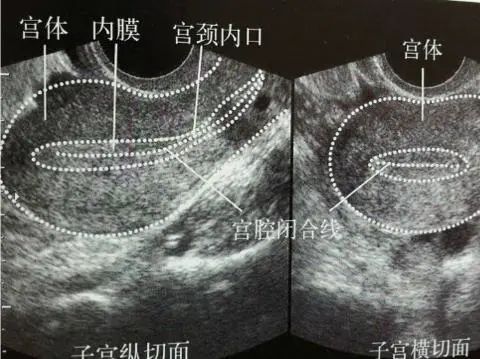

解读B超报告:子宫

子宫是产生月经和孕育胎儿的器官,位于骨盆腔中央,在膀胱与直肠之间。

1.子宫位置

B超报告中的第一个描述的就是“子宫呈前/后位”,位置到底代表什么?

子宫前位就是子宫体朝着腹部的方向弯曲,大多数人是这个位置,子宫后位就是子宫体向着背部的方向弯曲。无论子宫前位或后位都是正常的,而且受孕的几率都是相同的,没有差别。

2.子宫大小

子宫大小检查是通过触诊检查子宫体的长、宽、厚,从而判断子宫发育是否正常、有否病变的手段。

正常子宫大小是长5.5-7.5厘米,宽4.5-5.5厘米,厚3.0-4.0厘米,子宫颈长2.5-3.0厘米。子宫正常情况下,三个值相加大于12厘米。

3.子宫形态

正常的子宫是前后略扁的倒置梨形,外形是规整的,也就是比较圆滑,如果外形不规则或者呈球形,提示可能有肌瘤或者腺肌瘤。

解读B超报告:子宫内膜

子宫内膜子宫内壁的一层,它对雌激素和孕激素都起反应,可随着月经周期发生显著的变化。

女性月经周期的第5-14天属于增殖期,子宫内膜从0.5mm会长到3-5mm,甚至是达到8mm都是比较正常的。

女性月经的第15-28天属于分泌期,厚度则在10mm左右。

子宫内膜厚度问题一定要明白自己月经周期,处于哪个时期。子宫内膜增厚,不一定代表就是有疾病,需要进行复查B超,月经干净后3天内做是比较适合。

解读B超报告:宫颈

子宫颈位于子宫下部,近似圆锥体,长2.5~3cm,上端与子宫体相连,下端深入阴道。阴道顶端的穹隆又将子宫颈分为两部分,宫颈突入阴道的部分称宫颈阴道部。